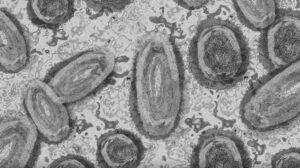

Maymun Çiçeği Virüsü Salgına Dönüşür mü?

Dünya Sağlık Örgütü, birçok ülkeye yayılmış durumda olan maymun çiçeği virüsünün yeni bir salgına dönüşmesinin beklenmediğini açıkladı.

Dünya'ya yayılmaya devam eden olan maymun çiçeği virüsü tüm Dünya'da yalnızca toplam 257 vaka bulunuyor.